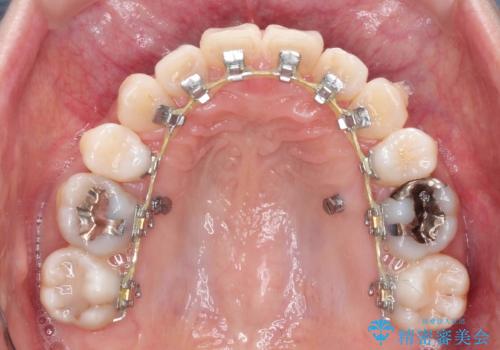

ハーフリンガル抜歯矯正 八重歯を改善する

- ハーフリンガル

- 小臼歯4本抜歯によるハーフリンガル・ワイヤー矯正を計画した。

シビアな八重歯がきれいに歯列にはいることにより、笑った時の印象などもかなり大きく変わります。